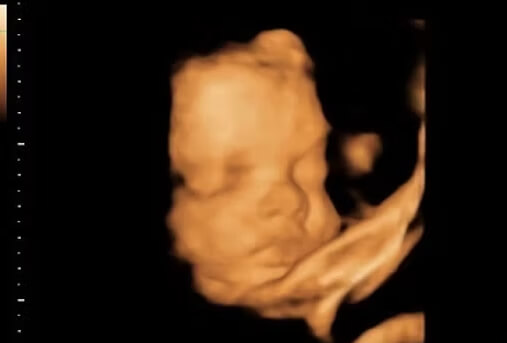

30 Haftalık Bebeğin Ultrason Görüntüsü

Öncelikle belirtmek isteriz ki bebeğinizin ultrason görüntüsü, internette gördüğünüz fotoğraflardan ve başka annelerin görüntülerinden farklı olabilir; çünkü her bebeğin anne karnındaki hareketleri ve duruşu farklılık göstermektedir.

• 30 hafta gebelik döneminde bebeğinizi anne karnında parmaklarını emerken görmeniz yüksek bir ihtimaldir; çünkü bu hareket sayesinde, gebeliğin 35. haftasına kadar bebeğinizin emme yeteneği gelişecek ve doğumdan sonra memeyi daha rahat kavrayarak emecektir.

• Ultrasonda bebeğinizin hıçkırdığını da görürseniz şaşırmayın; çünkü bebeğiniz dış dünyada nefes alabilmek için ritmik nefes alıyor ve bu da hıçkırmasına sebep oluyor.